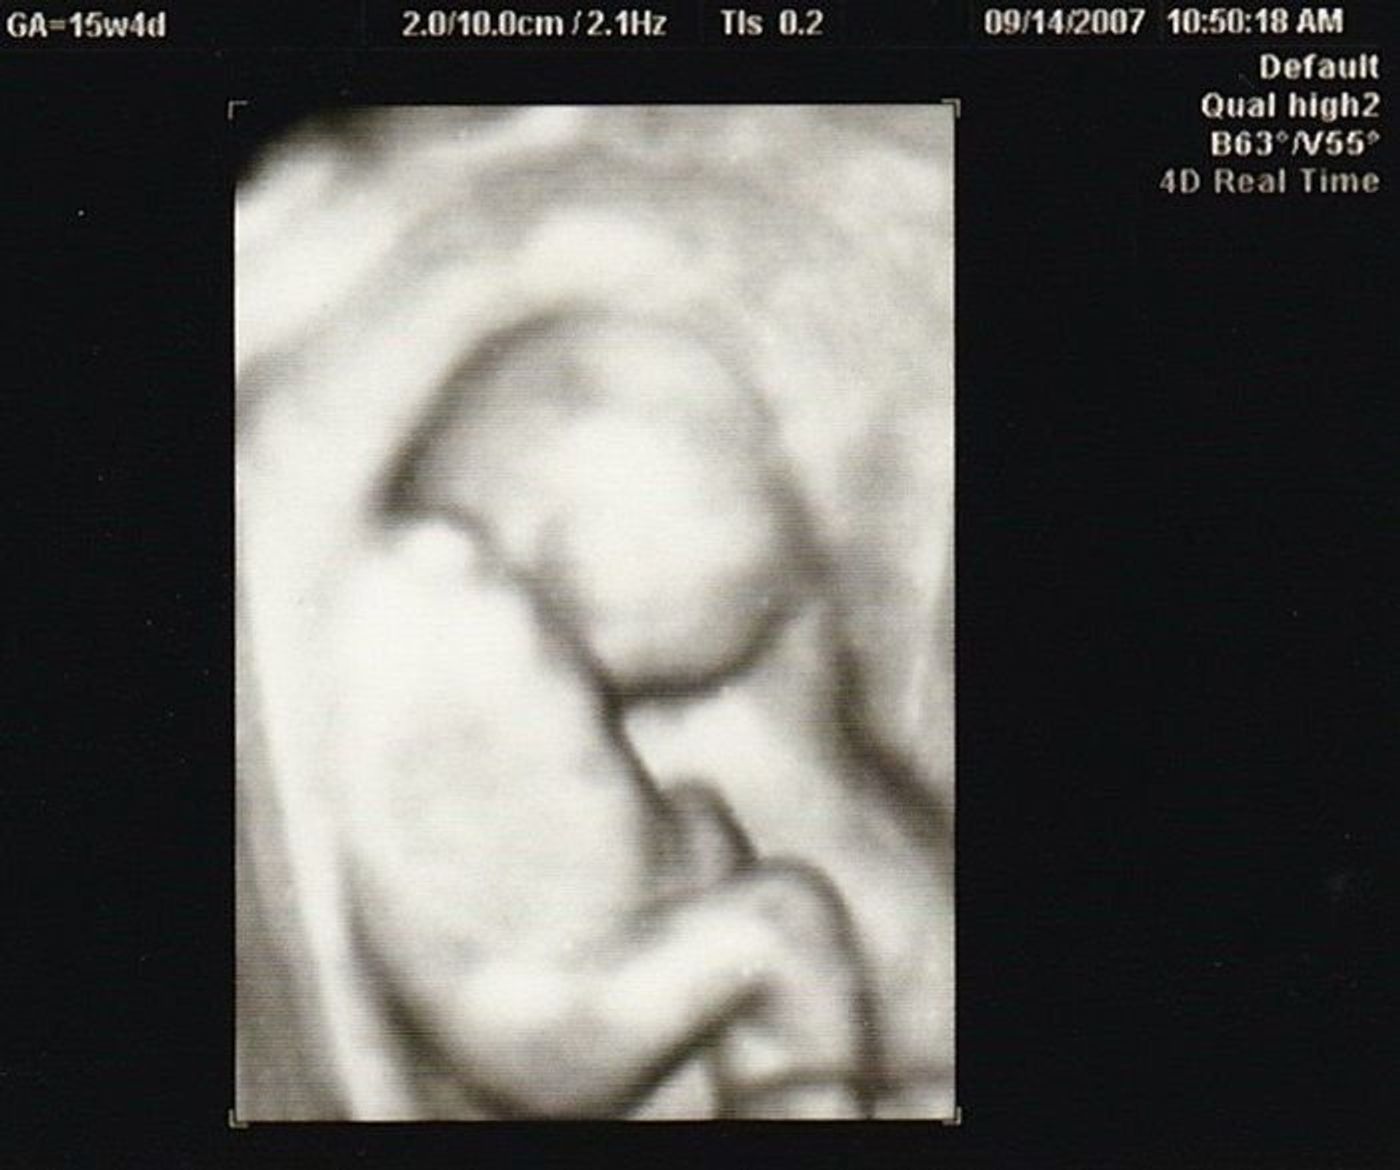

妊娠15週の手乗り赤ちゃん 15w4d さくら日記

15週目 赤ちゃん- 妊娠15週ごろの胎児の大きさ 身長約16cm、体重約100g(レモン1個くらい) 妊娠中期(16週~27週目)の胎児の成長経過 お腹もふっくらとし、妊婦さんらしい体つきになってくる時期。 お腹の中の赤ちゃんは、さらに体の各機能を発達させていきます。 15週目の胎児の大きさは、 身長が14~17cm程度、体重が100g程度 まで成長します。 胎盤と臍帯が完成して、胎児の体の基本的な組織は完成しています。 体の表面(皮膚)の発達も進み、指には爪や指紋、頭には髪の毛、体には産毛が生えてくるようになりました。

妊娠15週目の妊婦さんの身体 妊娠週数15週になると、胎盤が完成し赤ちゃんとママがへその緒でしっかりつながります。 また、お腹のなかの赤ちゃんの髪の毛を育てるホルモンが母体にも作用して、ママの髪の毛が抜けたり、体毛が濃くなったりすることがあります。 妊娠15週目の赤15週ごろに胎盤の基本構造が完成します おなかの赤ちゃんの成長12~15週ごろ 器官の形成が終わり、これからは体や手足の骨、筋肉などが発達していきます。 羊水の量が増え、その中で手足を動かすようになります。 皮膚は不透明で厚くなります。妊娠15週目の赤ちゃんはだいたい 身長が16cmほど、体重も40g100g くらいになります。 この時期の赤ちゃんは体の基本的な部分の形成がほぼ終わり、 体や手の骨・筋肉が急成長 します。羊水の中で激しく動くのでエコーではくるくると元気よく動く赤ちゃんが見られるかもしれませんね。